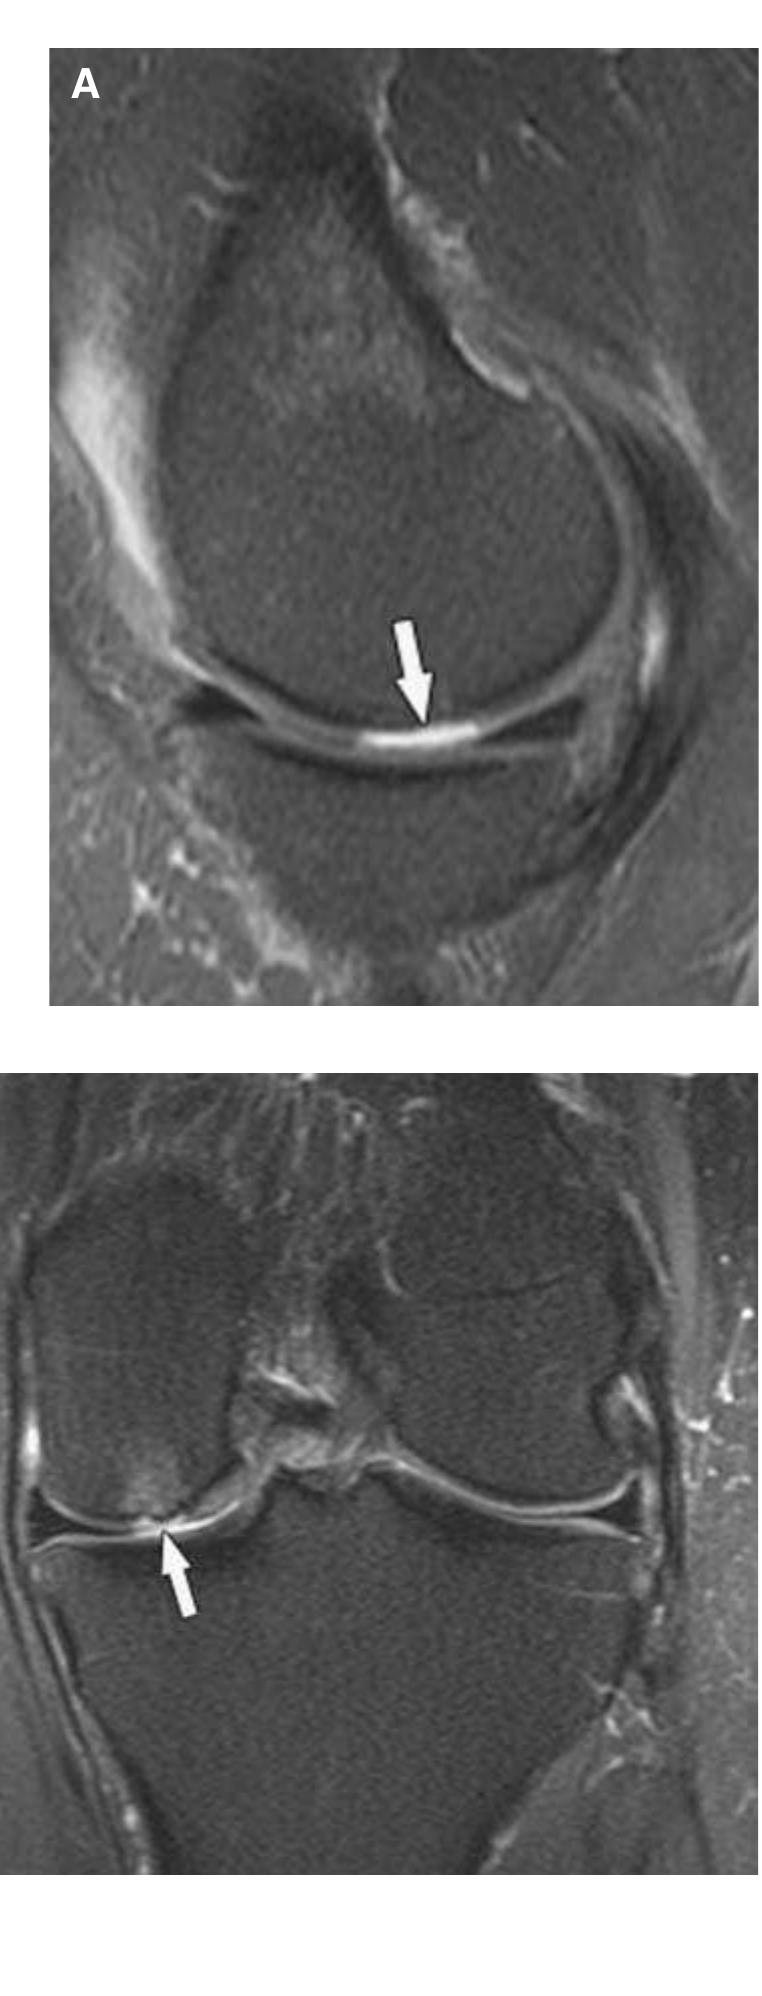

Virtually all types of collagenous tissues have been transferred in and around the knee joint for intra-articular and extra-articular ligament reconstructions. However, the mechanical properties (in particular, strength) of such grafts... more

The knee is an anatomically and biomechanically complex joint. Few studies have been published reporting the type and frequency of knee injuries. However, this information that may help to prevent, diagnose, and treat knee joint injuries.... more